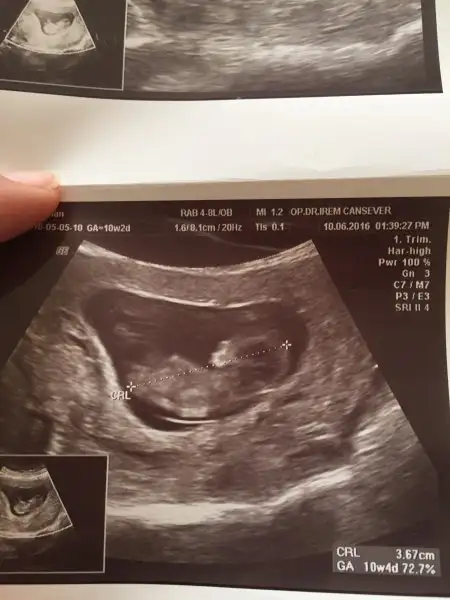

Havalianne__ . bana da yorum yapar mısın 8 ve 12 haftalık goruntuler.Karından usg ikisi de

6+0 vajinal 8+0 karından 8+2 vajinal